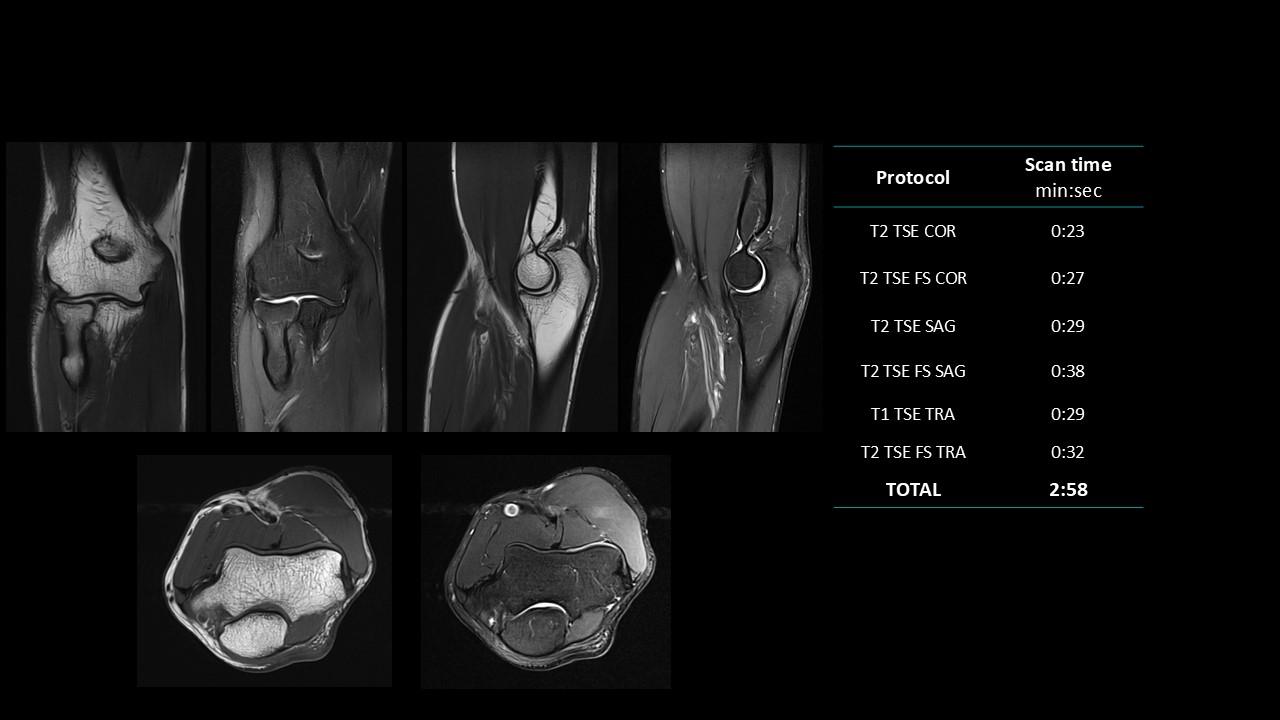

The Deep Resolve protocols are a set of advanced 3T MR imaging protocols designed to achieve high-quality diagnostic imaging with significantly reduced acquisition times.

Enabled by Deep Resolve, the AI-powered image reconstruction technology, these protocols deliver high-quality scans in approximately three minutes across a wide range of anatomical regions.

Developed and meticulously evaluated by Dr. Seong-ho Lee of Leaders Radiology Hospital in Seoul, Korea, the protocols integrate deep learning technology to enhance imaging efficiency while maintaining diagnostic detail.

By reducing scan duration, they improve workflow efficiency and patient experience without compromising image quality.